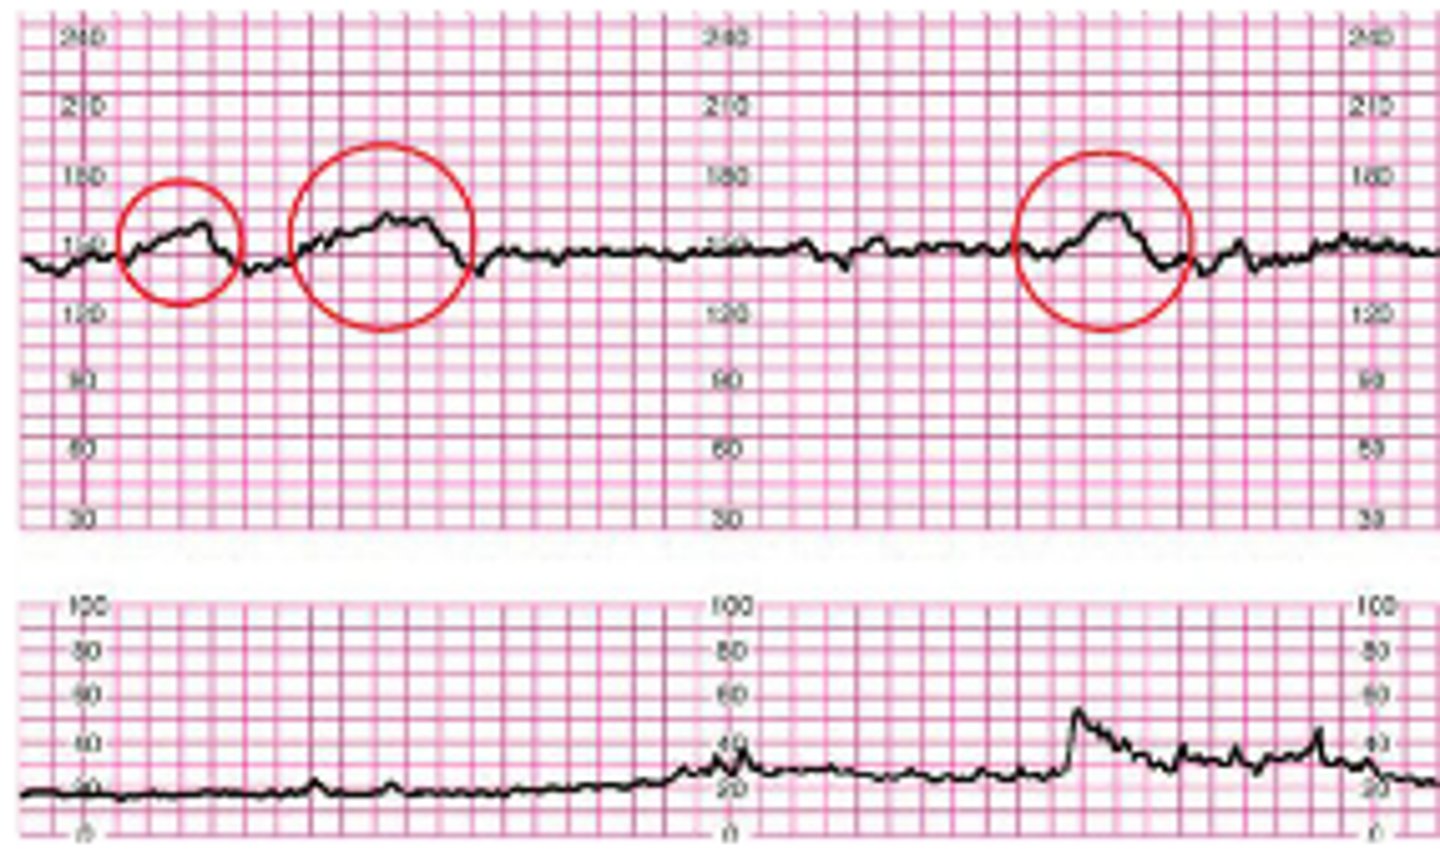

What do you do for an acceleration?

VEAL CHOP

High FHR - Okay

No interventions

Shows random upward bumps on FHR monitor

What do you do for a late deceleration?

Placental Insufficiency - "LION"

Stop Pitocin first if running.

What do you do for an early deceleration?

Head compression - Continue to monitor

Document findings

Shows low bumps on FHR monitor that align with contractions

What do you do for a variable deceleration?

Cord compression - "LION"

Shows random low bumps on FHR monitor that don't align with contractions.